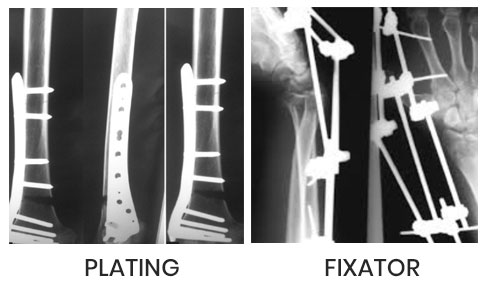

The centre runs 24 hrs emergency for accident cases managed by well equipped & trained staff all around the clock. Dr. Sagar Rane personally looks up all trauma cases & operates himself. All surgeries one done under C-ARM (scan) machine. So perfect results are achieved. He does vascular surgery /repair himself.

Under C-ARM all surgeries done through key hole incision and under bone scan control which gives 100% results.